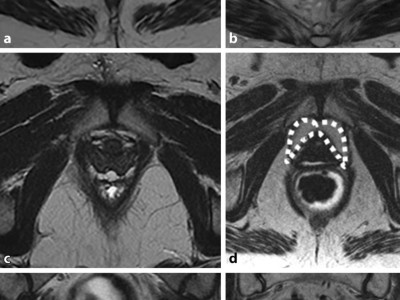

Eine ligamentäre vaginale Prolapskorrektur erlaubt mittlerweile Symptomheilungen in hohen Prozentsätzen, bei Harndranginkontinenz, Nykturie oder anderen mit urogenitalem Deszensus assoziierten Symptomen. Wichtig für den Erfolg ist eine anatomisch gute operative Korrektur. Aktuelle Techniken müssen diesbezüglich auf den Prüfstand gestellt werden.

Bildnachweise